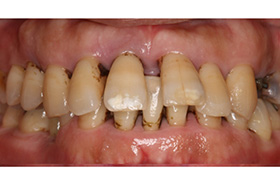

歯周病でお悩み・

不安な方のために

歯周病は治せます。なるべく歯を残せるような治療をしますが、再発を防ぐためには、その患者様の協力が非常に必要です。年をとっても自分の歯で食事ができるようにするためには、きちんとしたケアを実践しましょう。

再生療法

(歯周組織再生療法)

歯周病などにより、顎骨や歯根膜を失った際の治療法です。エムドゲインは哺乳類由来のタンパク質で、歯の発生を促す作用があります。骨を失った箇所にエムドゲインを塗布することで、造骨細胞などの歯の周辺を形作る細胞群が活性化されて、顎骨およびその周辺組織が再生されます。